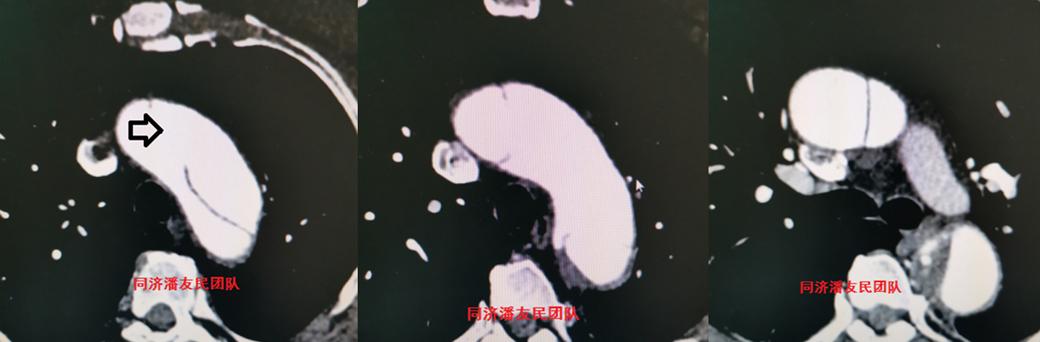

在那里,我被安排了一系列神经系统方面的检查,其中包括了颈部血管彩超(图2)。

没想到,这个检查让神经内科的医生们紧张起来。

为了追溯左颈总动脉夹层的来源,是单发的颈动脉夹层,还是主动脉夹层影响到颈动脉?

于是,胸腹主动脉CTA被安排(图3~5),结果显示夹层病变从升主动脉远端开始,累及到主动脉弓部,其中左颈总动脉及左锁骨下动脉均累及。